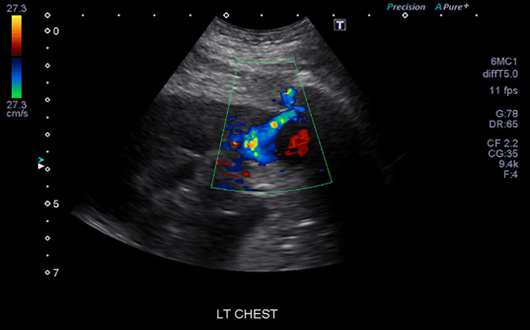

Ultrason Ankara

Ses dalgalarının teknoloji ve tıp alanlarında pek çok kullanım alanı mevcuttur. Bunlardan biri olan ultrason, bir tıbbi görüntüleme yöntemi olup ses dalgaları yardımıyla vücudun iç kısmında yer alan doku ve organların genel hatlarıyla görülebilmesini sağlar. Ultrason meme ve tiroid taraması başta olmak üzere pek çok alanda tanı ve tedavi imkanı sunar.